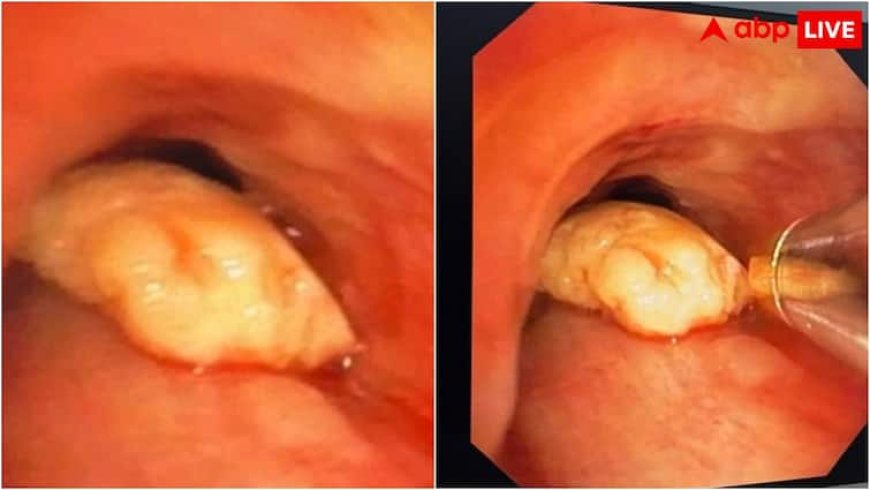

अखिल भारतीय आयुर्विज्ञान संस्थान (AIIMS), गोरखपुर ने एक ऐसी महिला की जान बचाई है, जिसकी सांस की नली में गलती से काजू फंस गया था. यह महिला पिछले चार दिनों से खांसी, सांस फूलने और भारी बेचैनी जैसी समस्याओं से जूझ रही थी, जिसके बाद 53 वर्षीय महिला को उसके परिजन इलाज के लिए AIIMS में इलाज के लिए लेकर आए थे.

महिला को बीते कुछ दिनों से खांसी आने और सांस लेने में तकलीफ थी, जिसके बाद परिजन उसे स्थानीय अस्पताल लेकर गए. जब महिला का सीटी स्कैन और एक्स-रे में हुआ तो उसकी सांस की नली में काजू का एक टुकड़ा फंसा पाया गया. स्थानीय अस्पताल में एंडोस्कोपी की मदद से उसे निकालने की कोशिश की गई, लेकिन वह प्रयास सफल नहीं रहा. ऐसे में महिला को AIIMS गोरखपुर में भर्ती किया गया.

AIIMS के पल्मोनरी मेडिसिन विभाग के डॉ. सुबोध के नेतृत्व में डॉ. कनुप्रिया और डॉ. राघव की टीम ने यह जटिल ब्रोंकोस्कोपी प्रक्रिया अंजाम दी. इस प्रक्रिया के लिए वीडियो-ब्रोंकोस्कोप, क्रायो मशीन और डॉर्मिया बास्केट जैसे अत्याधुनिक उपकरणों का इस्तेमाल किया गया. यह ऑपरेशन ओटी में अत्यंत सतर्कता और तकनीकी सटीकता के साथ किया गया. इस दौरान एनेस्थीसिया विभाग की डॉ. विजेता बाजपेई और डॉ. प्रियंका द्विवेदी ने संपूर्ण प्रक्रिया में सहयोग प्रदान किया. दोनों विभागों की इस संयुक्त कार्यप्रणाली ने महिला को एक नई ज़िंदगी दी. ऑपरेशन के बाद महिला की हालत स्थिर बताई जा रही है और वह सामान्य रूप से स्वस्थ हो रही हैं. AIIMS गोरखपुर की कार्यपालक निदेशक मेजर जनरल डॉ. विभा दत्ता की देखरेख और मार्गदर्शन इस ऑपरेशन को किया गया. उनकी प्रेरणा और संगठनात्मक दक्षता ने चिकित्सा दल को सटीक और समर्पित ढंग से कार्य करने के लिए प्रोत्साहित किया.